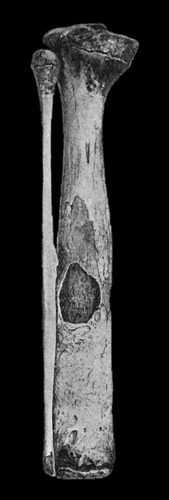

122.Sequestrum of Femur after Amputation 453

123.New Periosteal Bone on Surface of Femur from Amputation Stump 454